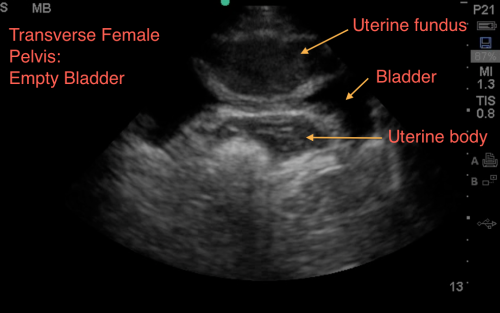

The Suprapubic Views

The suprapubic view on the eFAST exam is generally the last of the four views performed.

Both Longitudinal & Transverse views are required

Theoretically, given its dependent anatomical position, one may conclude that it should in fact be the most sensitive view to visualize free fluid; unfortunately, the literature has negated this theory – and in fact this can often be the least sensitive view, largely in part of human error, and especially in pelvic fractures.

Anatomically, when we scan the suprapubic area in both transverse and longitudinal planes, there’s a lot that we see –the bladder, bowel, pelvic bones, pelvic organs, and rectum to name a few.

This might make it harder for us to visualize free fluid, and separate it out from these other structures. But here’s a few tips to help overcome these limitations. Begin by placing your curvilinear probe just above the pubic symphysis, aiming inferiorly/caudad into the pelvis.

1. Look through a full bladder. - The suprapubic view is best visualised using a filled bladder as the acoustic window. Not all trauma patients come in with a full bladder....

It is important to note, that if your patient has an empty bladder, it makes it tough, you may have to repeat scan after hydration, when the bladder is more full. With an empty bladder your ability to adequately discern free fluid is very limited. Mostly due to gas scatter from bowel, inadequate depth adjustments, and inability to discern bowel fluid from free fluid.

2. Adjust your depth - More often than not, when it is time to scan the suprapubic area, your depth is set too deep from scanning the upper quadrants or cardiac views. We often find that a depth of about 13cm to 16cm optimizes your view. The goal is to have your bladder centered on the screen, to easily visualize the areas surrounding the bladder

3. Adjust your gain – The bladder is a fluid filled structure, and as mentioned before, fluid is the “lover” of ultrasound, allowing structures deep to it to be well visualized, however this often creates an artifact called “posterior acoustic enhancement” that produces a hyperechoic and bright area deep to the bladder. This makes it hard to visualize anechoic or black free fluid.

One of the biggest pitfalls is not decreasing your gain to accommodate for this, and limiting your ability to pick up anechoic free fluid.

A good rule of thumb, is to ensure that you can easily visualize pelvic organs. If you are able to identify a uterus or a prostate easily, that usually means you have adjusted your gain appropriately.